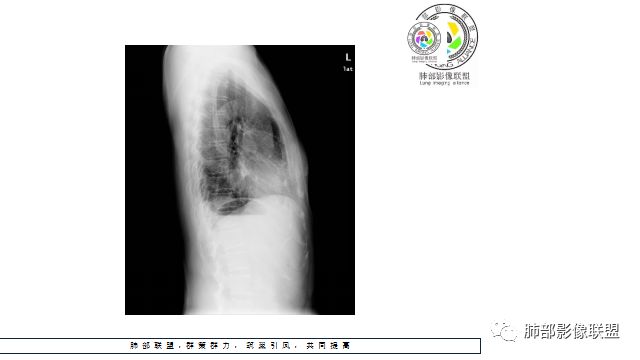

看似繁花似锦,也会暗流涌动。一张普通的胸片在基层很常见了,在一张看似正常的胸片后面隐藏了什么?敬请各位来分析。

Shelia:侧位心后间隙变小,下肺野与心影重叠区怀疑有斑片影

正位实在看不出什么问题

M-Imaging :盘状不张不是,盘状不张,胖人腹压高多见远方:如南大所标示,标准答案。正位提示左肺下野与膈面重叠密度增高影,边缘光滑,侧位可再定位具体一点后肋膈角区密度增高影,具体是肺内肺外都有可能,盘状肺不张、肺内肿块、肺外病变(胸膜来源和膈肌来源)等都可以。我的体会常规正片再加负片结合这个肯定不会漏的,负片很有价值,平片发现问题就好,具体我们还是进一步CT检查了。

远方:基层医院很多都是X线为主,胸片占了一半以上,专科除外,正侧位片往往不重视侧位,临床医生也经常未要求侧位,考验我们影像医生了。这个单凭正位往往就漏了。恰好病变上缘与膈肌面比较重合。